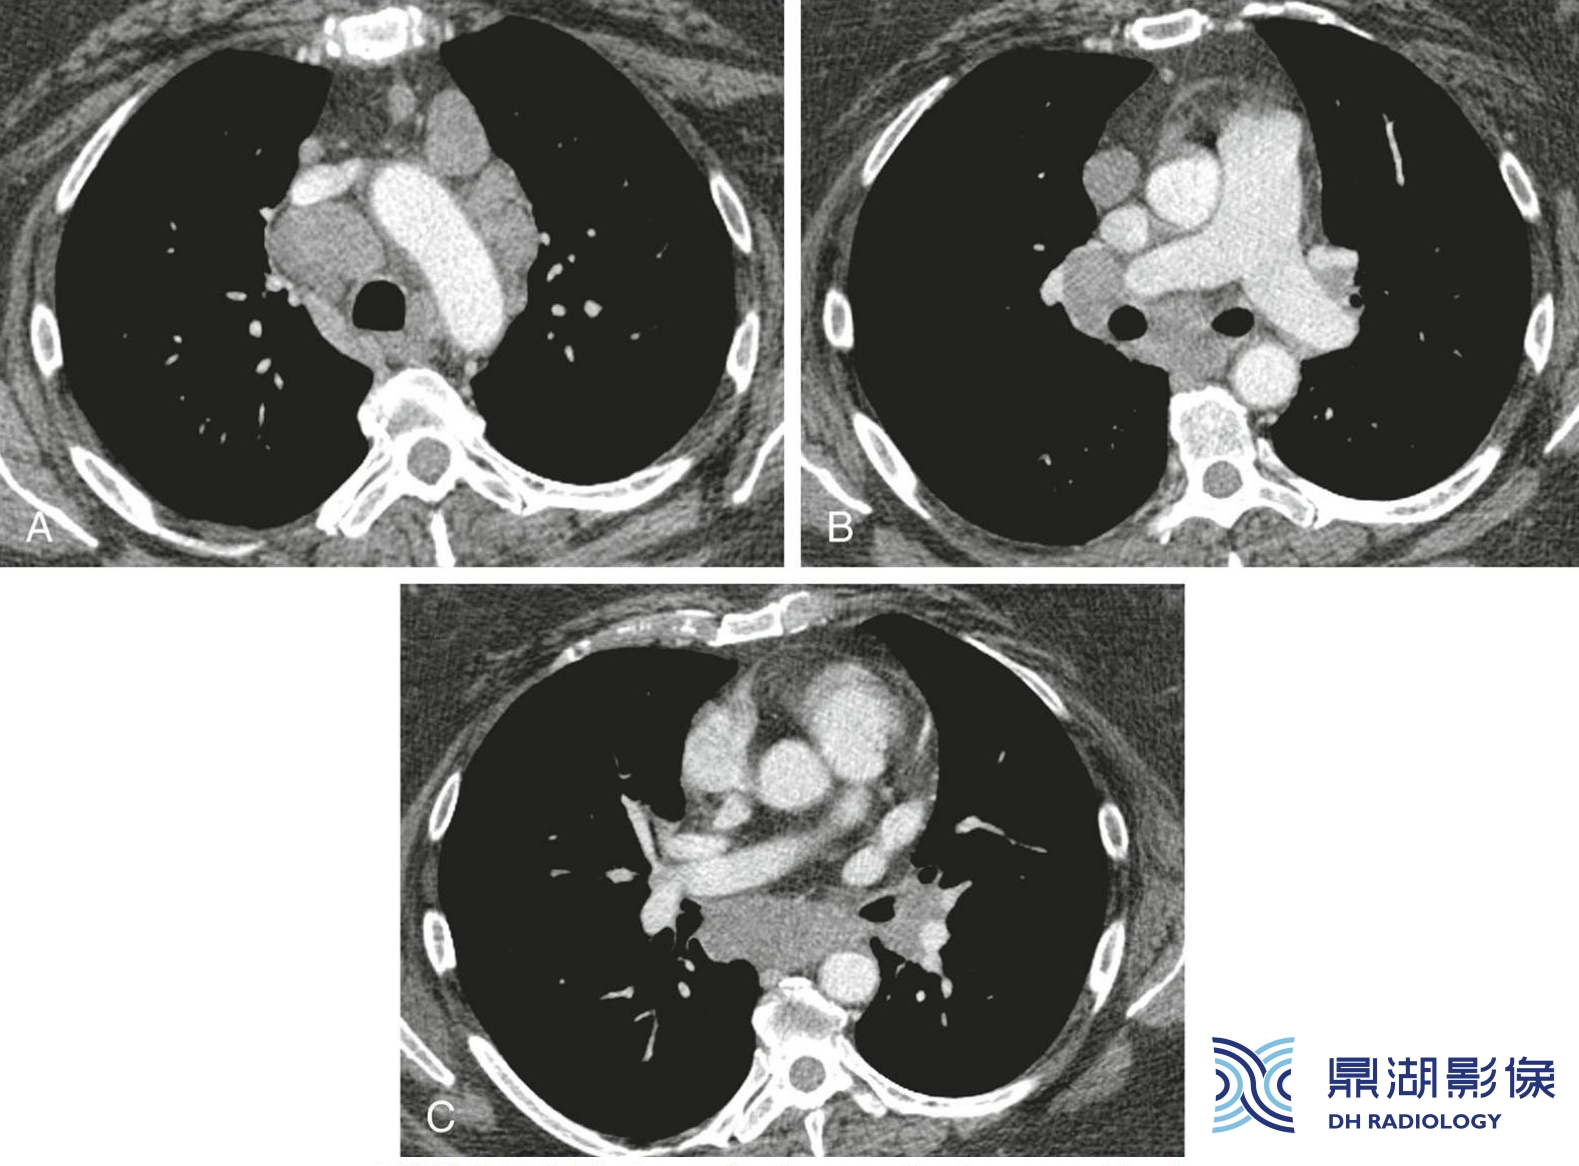

208584f2131654e0ee4ca26ff4242a52.jpg

结节病伴淋巴结肿大。A至C.气管旁、主肺动脉窗、隆突下及肺门区可见对称性淋巴结肿大。结合对称性肺门受累,强烈提示结节病。但是淋巴结肿大并不是HRCT诊断结节病的必要条件。